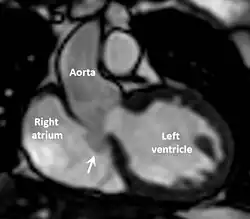

| Diagnostic method | Echocardiogram, cardiac CT scan, cardiac MRI scan |

The first step in diagnosis is typically transthoracic echocardiography. However, if surgery is planned or if the standard echocardiogram lacks sufficient detail, then one or more additional studies are recommended. These studies include transesophageal echocardiography, 3D echocardiography, CT Angiography and aortic angiography.[4] Cardiac MRI may be another option.[2]